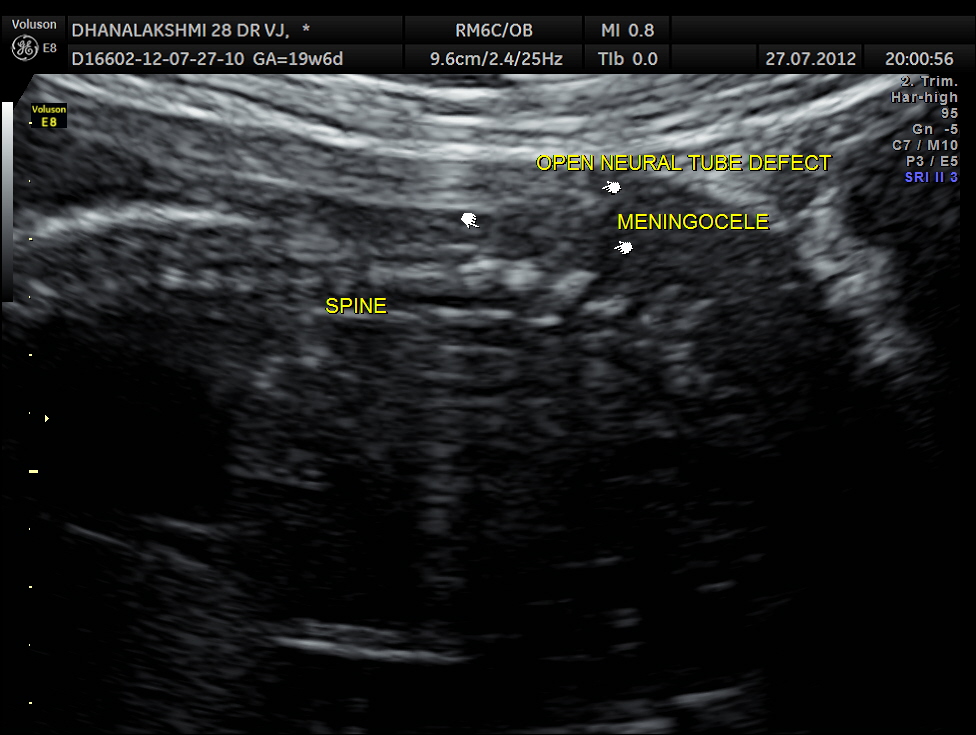

careful examination of the fetal spine revealed the following